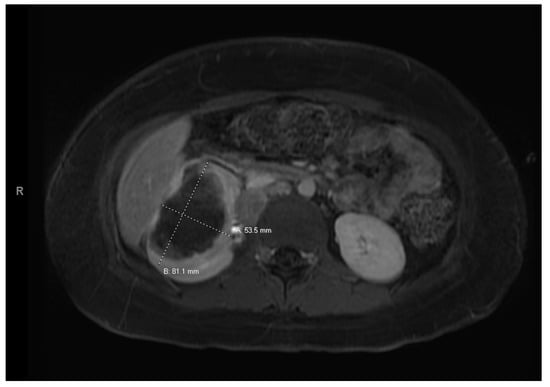

At age 15, she presented to an outside ER with a 2–3-day history of worsening right lower quadrant abdominal pain, nausea and occasional vomiting. She also had a history of a 20-lb weight loss over the past few months due to decreased appetite. CT scan showed a right renal mass 7 cm in size. She was transferred to our hospital and MRI abdomen/pelvis showed an indeterminate left adrenal nodule (Figure 3) and a large, solid, peripherally enhancing right renal mass with central heterogeneity measuring 8.1 × 5.4 × 8.7 cm (Figure 4). It also showed retroperitoneal lymphadenopathy with a retrocaval node at 4.1 × 2 cm, superior retrocaval node at 2.6 × 1.6 cm and an inferior precaval/aortocaval node at 1.5 × 0.9 cm. There was also a right lung nodule noted on a chest CT (Figure 5). She then had a baseline positive emission tomography (PET) scan which again showed the right renal mass, concerning for primary renal cell carcinoma, FDG avid retroperitoneal lymphadenopathy, concerning for metastasis and small bilateral pulmonary nodules, concerning for metastasis. She underwent a biopsy of the right renal mass, which was inconclusive. She underwent a second biopsy and was found to have RCCU-MP manifesting as a high-grade malignancy with loss of SMARCB1 by immunohistochemistry in the absence of a sickle hemoglobinopathy.

Figure 4. Right renal tumor.